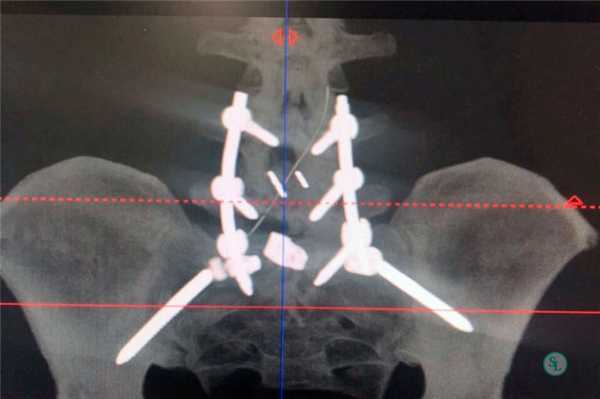

Транспедикулярная фиксация позвоночника

Транспедикулярная фиксация или ТПФ - операция, при которой позвонки фиксируются и стабилизируются при помощи специальных имплантов (транспедикулярных винтов). В каждом позвонке есть точка ввода винта, которую установил в 1985 году Рой Камилл — это точка пересечения поперечного отростка позвонка с верхнем суставным отростком. С помощью специальных инструментов в эту точку, вкручиваются винты определяя анатомически правильное расположение позвоночника, тем самым излечивая заболевание. Первые попытки установки имплантов были в 60-70 гг. прошлого века и с тех пор является «золотым стандартом» в лечения переломов и различных заболеваний позвоночника.

ТПФ выполняется под рентгеновским контролем, что позволяет хирургу точно контролировать каждое движение и избежать повреждения близкорасположенных анатомических структур. Чаще для этого используется ЭОП или КТ.

Очень важно при установки винтов соблюсти следующие моменты: отсутствие пространства между костью и винтом, исключение травматизации нервных и сосудистых структур или смежных дугоотросчатых суставов. Импланты устанавливаются согласно размерной линейки каждого позвонка и винта, бикортикально не касаясь замыкательных пластин.